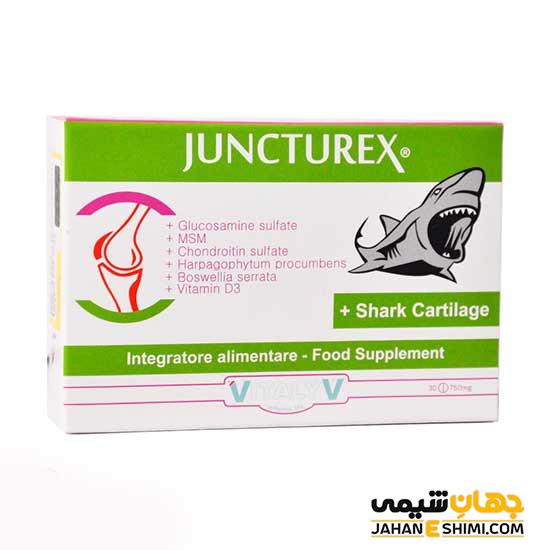

قرص جانکتورکس ویتالیو چیست؟ موارد و نحوه مصرف و عوارض آن

قرص جانکتورکس ویتالیو ترکیبی از گلوکزامین، ام اس ام، کندرویتین سولفات، شارک کارتیلیج و ویتامینD3، عصاره گیاهان هارپاگوفیتوم و بوسولیا سراتا است و سبب تقویت عملکرد مفاصل و سبب نگهداری از استخوان ها میشود. در نشریه جهان شیمی فیزیک از انواع مکملها مقالاتی منتشر شده است. در این مطلب اطلاعاتی در مورد قرص جانکتورکس ویتالیو در اختیارتان قرار میدهیم.

قرص جانکتورکس ویتالیو چیست

قرص جانکتورکس ویتالیو ترکیبی از گلوکزامین، ام اس ام، کندرویتین سولفات، شارک کارتیلیج و ویتامین D3 به همراه عصاره هارپاگوفیتوم و بوسولیا سراتا است. سبب تقویت عملکرد مفاصل و جذب کلسیم و فسفر می شود

موارد مصرف قرص جانکتورکس ویتالیو

تقویت عملکرد مفاصل و نگهداری استخوانها

نحوه مصرف قرص جانکتورکس ویتالیو

دو قرص در روز به همراه آب مصرف گردد.

احتیاط در مصرف قرص جانکتورکس ویتالیو

قرص جانکتورکس ویتالیو مکمل غذایی است و برای تشخیص، پیشگیری و درمان نیست.

ویژگی قرص جانکتورکس ویتالیو

تقویت عملکرد مفاصل

کاهش التهاب و درد مفاصل

پیشگیری از فرسودگی مفاصل

مصرف مکملها و قرص جانکتورکس ویتالیو

مصرف قرص جانکتورکس ویتالیو در بهبود مشکلات مفاصل و آسیبهای استخوانی موثر است.

شرایط نگهداری از قرص جانکتورکس ویتالیو

قرص جانکتورکس ویتالیو، دور از دید اطفال و نور و در جای خشک و خنک قرار دهید.